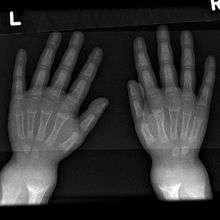

- Widening of wrist[5] raises early suspicion, it is due to metaphyseal cartilage hyperplasia.

An X-ray or radiograph of an advanced sufferer from rickets tends to present in a classic way: bow legs (outward curve of long bone of the legs) and a deformed chest. Changes in the skull also occur causing a distinctive "square headed" appearance (Caput Quadratum). These deformities persist into adult life if not treated. Long-term consequences include permanent bends or disfiguration of the long bones, and a curved back.[6]